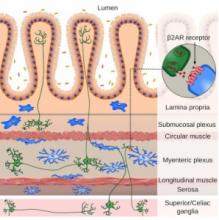

Actualité publiée il y a 10 années 2 moisMaladies de l'INTESTIN: Les neurones prêtent main forte aux cellules immunitaires